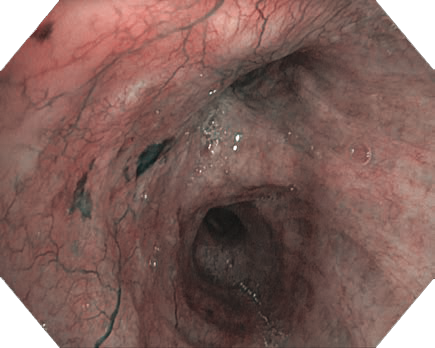

-              NBI (Narrow Band Imaging)粘膜表層の血管走行が強調表示され、高精度な診断をサポートするNBI。新しいスコープではNBIの明るさが向上し、血管構造がさらに観察しやすくなりました。